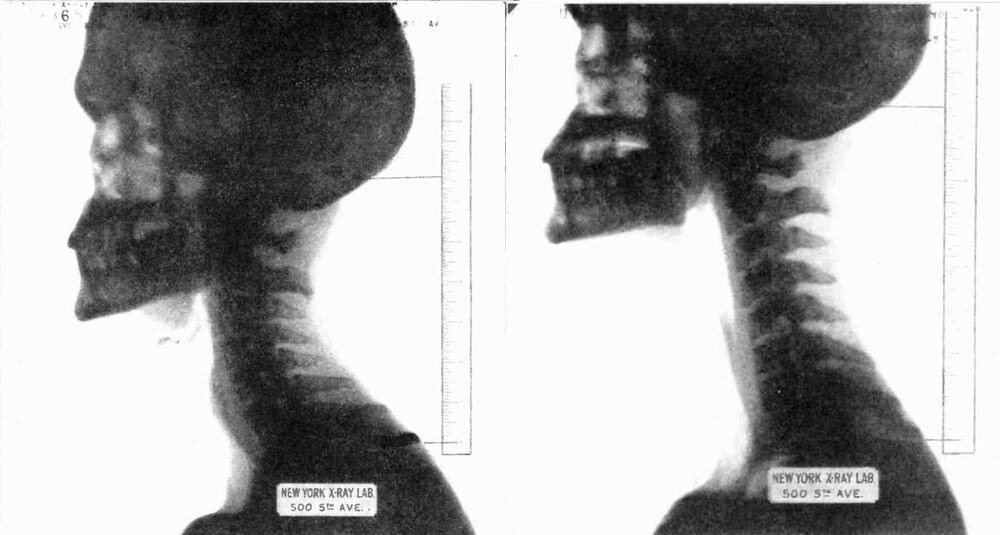

Сентябрьский номер журнала Science and Invention за 1927 год был посвящён объяснению того, как Уиллард растёт по команде. Редакторы сделали ему рентген и определили, что искривление позвоночника у «Человека, который растёт» возможно, больше, чем у обычного. Исключительно мышечными усилиями он способен заставить позвонки принять почти идеальную прямую линию. Таким образом он может увеличить длину своей шеи.

Рентгеновский снимок